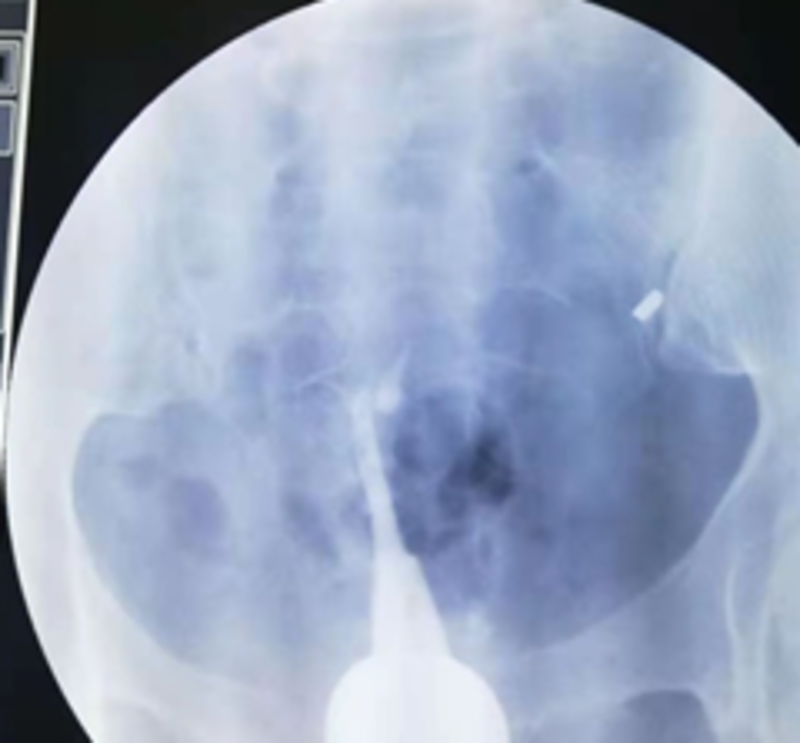

这是2年前的一个病例。一位广州市荔湾区桥中街村民邓XX,43岁,20年前第一胎生儿子后结扎。开放二胎后做输卵管吻合术,术中腹腔镜通液显示输卵管不通。术后第3个月找我做造影。我第一次做造影时造影导管插入宫颈浅进入不了宫腔,球囊固定不了造影管。我就用探针探测看看,探针只能进去宫腔3.5厘米,就在宫颈外口注造影剂,显示宫腔呈一长条状,形态同一段探针相仿,见图像1。我虽然是放射介入科医生,但是我是妇科生殖专业博士,在读妇科博士前,还专门进修妇科6个月,做过宫腹腔镜手术,插造影管对我来说是很简单的手术,基本上没有插不上造影管。做不了造影。但是,为诊断清楚,就没收费用,预约第二天请广州市红会医院原妇科主任,著名妇科腔镜专家陈燕辉主任出诊时,请陈主任插管再做一次造影。第二天,陈主任插造影管后,也固定不了造影管,就用探针探测宫腔,考虑重度宫腔粘连,宫腔近封闭,就用探针分离一下宫腔。我又在宫颈外口注入造影剂进行造影,显示宫腔近呈单叶片状,形似单角子宫,见图像2。然后追问病史,患者才讲10年前子宫大出血,做一次刮宫后再也没有月经。第二个月陈主任门诊行宫腔镜探查术证实重度宫腔粘连。重度宫腔粘连输卵管开口封闭,不管是做试管还是自然怀孕都不行,需要处理宫腔粘连才行。由于患者年纪大,和家属商量后就放弃再怀孕。因此,就没有处理宫腔粘连。符合宫腔粘连对于没有生育要求和没有痛经等不适者可以不手术的治疗原则。

结扎图2.png

图二